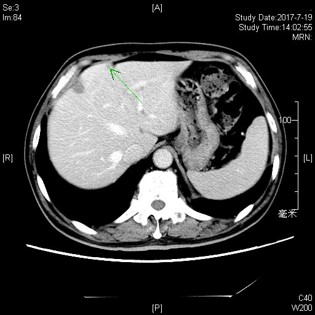

2016-03-03复查CT:左下肺结节增大,考虑转移;肝脏新见结节,不除外转移;上腹术后改变较前相似;右甲状腺病变基本同前。

2016-05-12复查CT:左下肺结节缩小,考虑转移;肝脏结节,较前增大,拟转移;上腹术后改变较前相似;右甲状腺病变基本同前。

RECIST1.1: 肝脏病灶8.7毫米增大到12.1毫米,左下肺病灶14.5毫米缩小到8毫米。疗效评价:稳定。

后于2016-05-16行肝脏射频消融治疗。